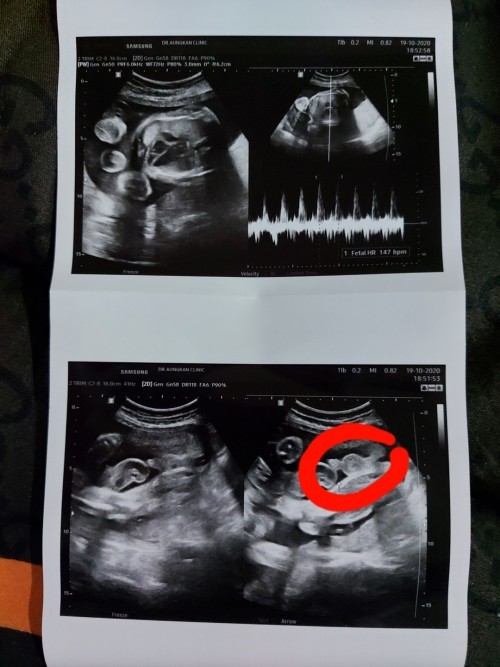

ชายจ้า ชัดมากๆมาเปนพวง😆😆

ซาวด์ตอน27weekจ้า ผู้ชาย_จ้า